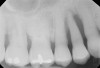

GTR, however, is still a viable option because there is consistency in published data—treating a vertical osseous lesion with this technique results in more clinical attachment gain than just open-flap debridement without performing GTR.46 The success rate in smokers, however, is significantly lower than in nonsmokers.47 Figure 11 and Figure 12] show a case in which tooth No. 22 had a large distal defect. Figure 13 shows the 6-year re-entry photograph, and Figure 14, the 6-year posttreatment radiograph, demonstrating complete clinical fill of the defect. Factors to consider in GTR include defect size (at least 3 mm to 4 mm), number of defect walls (at least two bony walls, but a three-wall defect is the most predictable to treat; Figure 15 shows a one wall defect, which is not graftable), furcation status (furcations are less predictable to obtain increased clinical attachment levels46), and mobility.48 However, patient compliance is critical in regard to both short-term and long-term success rates with GTR.

Figure 12  Radiographic view of the case seen in Figure 11.

Figure 12

Figure 14  Radiographic view of the case seen in Figure 13 showing complete bone fill of the periodontal defect (the bone graft used was mostly radiolucent).

Figure 14